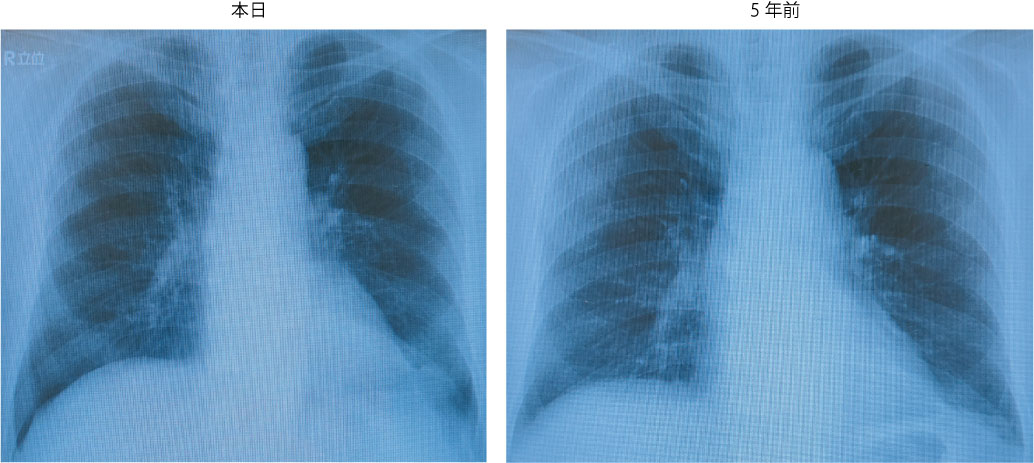

# 肺腫瘍疑い

<画像所見>

・胸部レントゲン

・胸部CT:肺野、縦隔に異常なし